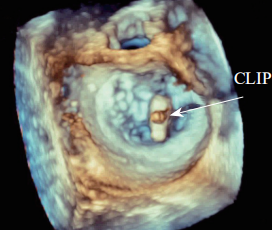

超声心动图在MR介入术中起着不可或缺的作用,下面以目前最为成熟的经导管二尖瓣夹合术MitralClip为例,阐述MR介入术中的超声评价。MitralClip是在经食管超声心动图实时监测和引导下的操作,所有的导管操作由经食管超声心动图监测和引导[17]。经食超声心动图首先引导房间隔穿刺,使得房间隔穿刺点距二尖瓣瓣环平面的高度为3.5~4.0 cm(图12)。之后,经食管超声心动图引导输送系统进入左心房并调弯、顶端垂直指向二尖瓣口。接着,经食管超声心动图引导夹合器在二尖瓣上方定位、夹合器进入左心室、引导夹合器捕获和夹合瓣膜。夹合器捕获瓣膜位置,应该位于彩色多普勒显示反流束最大处。在整个手术过程中,两个超声视野非常重要,为手术的工作切面,其中X-plane双切面,包括三腔心切面(左心室长轴切面)及二尖瓣交界处二腔心切面(图13)。三腔心切面可以显示二尖瓣A2、P2的位置,捕获瓣膜前二尖瓣夹合器应该在这个切面显示为V字形,此时瓣夹合器臂与二尖瓣开放线垂直,分别位于A2、P2的位置,在该切面通过调整夹合器位置可使得夹合器更靠近前叶或后叶;二尖瓣交界处二腔心切面显示P1、A2、P3,捕获瓣膜前二尖瓣夹合器在该平面应该为直线形,在该切面通过调整夹合器位置可使得夹合器更靠近瓣环内交界(P3或A3)或外交界(P1或A1)。另外一个工作切面为三维超声心动图的“二尖瓣外科视野”,可以整体观察夹合器的位置、臂指向的方向(图14)。目前有限经验显示,经心尖二尖瓣夹合术(ValveClamp)术中超声心动图指导和MitralClip总体上类似,但仍有部分差异,其超声心动图规范尚在探索中。

图 14 经食管实时三维超声心动图显示二尖瓣夹合器(CLIP)位于二尖瓣口中央并与二尖瓣前后叶垂直(箭头所示)